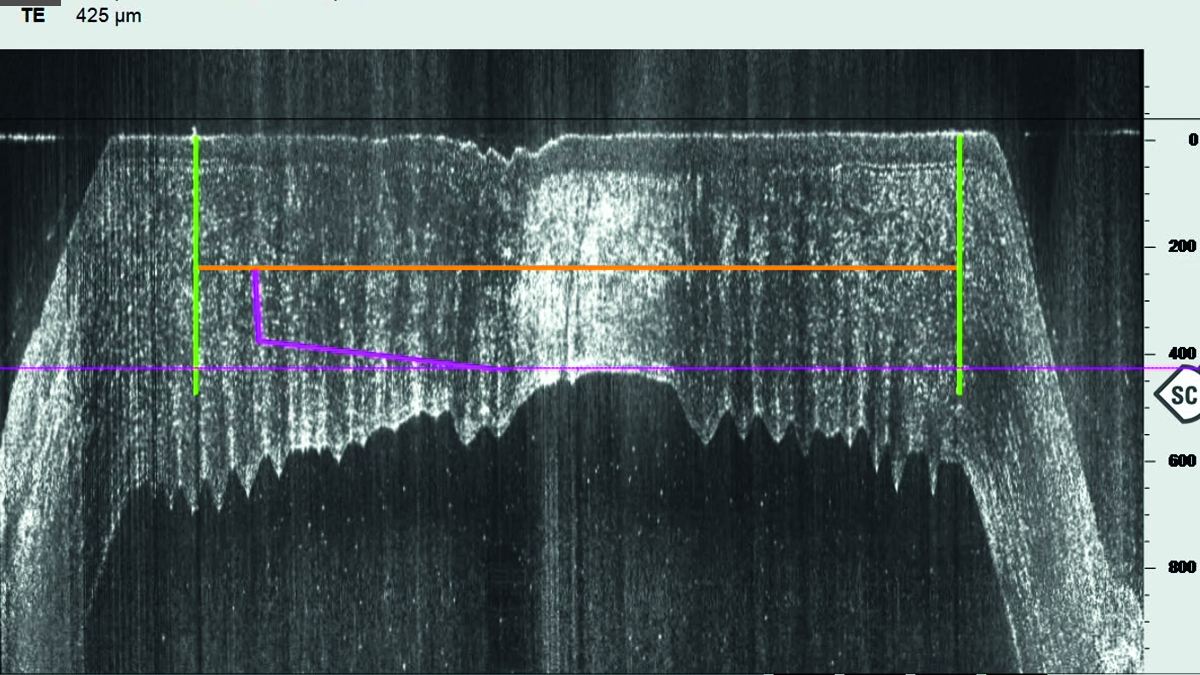

Femto-Lasik und Femto-DALK mit intraoperativer OCT

Anhand von zwei Fallberichten wird dargestellt, wie Femtosekunden-Laser und intraoperative OCT zu erfolgreichen OP-Verläufen beitragen: Bei der Umsetzung einer Monovision 22 Jahre nach myoper Mikrokeratom-LASIK sowie bei der DALK als Alternative zur perforierenden Keratoplastik.